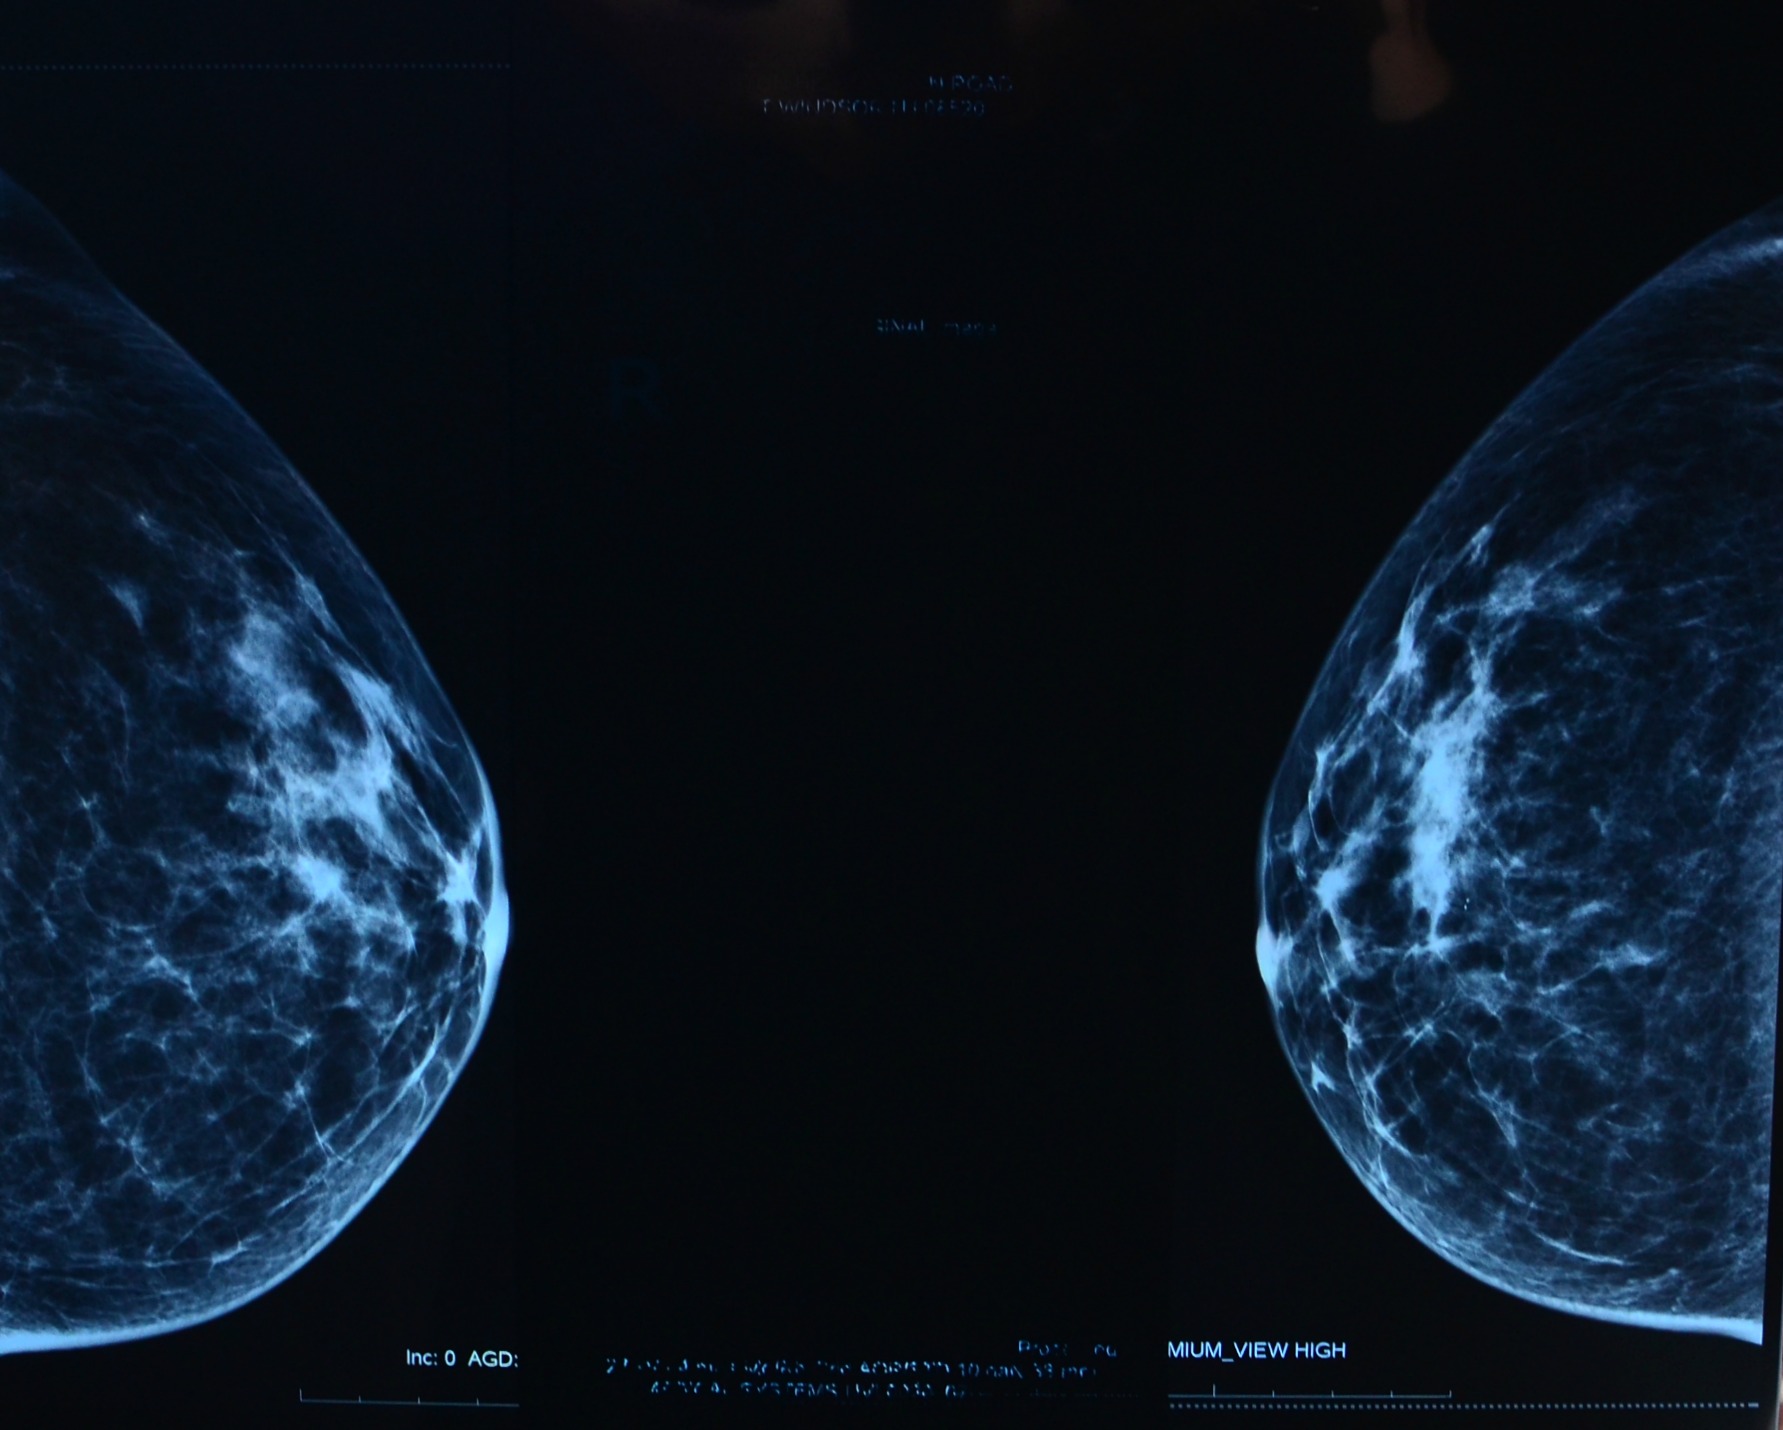

Screening has come a long way in just a few decades (it’s been 40 years since mammograms became standard practice), producing high-quality images that help doctors treat patients. But it can still do better.

Researchers and biotech companies striving to reduce overtreatment and overdiagnosis come out with new screening tools all the time. But before they make their way into local hospitals, those tools need to be vetted by experts to ensure that the technology offers demonstrable benefits to patients. Tomography, which produces 3D images of the breast in addition to a conventional mammogram, is one such tool. Initial studies indicate that it’s pretty useful—it produces sensitive images that can reduce the number of patients who are called back for additional screening, saving doctors time and reducing patient anxiety. But researchers are still debating tomography’s benefits in the long term. “We’re figuring out how much better [tomography] might actually be,” Smith says.